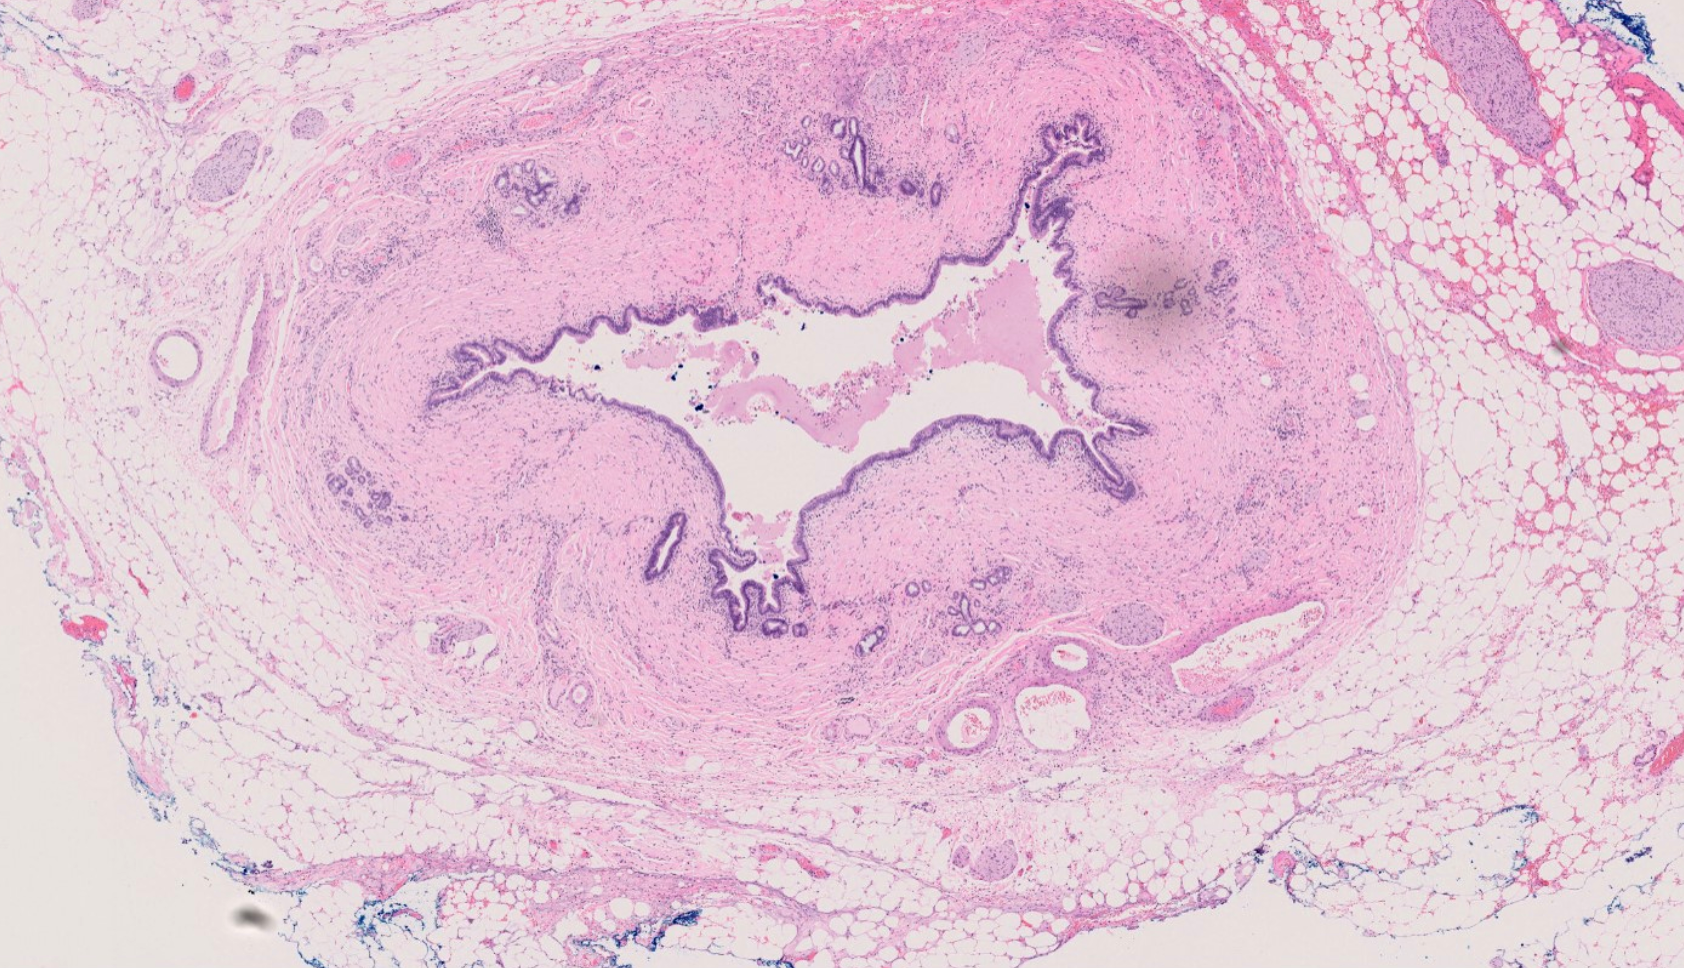

Systemic infection of acute inflammation & infection of bile ducts resulting from combination of biliary obstruction and bacterial bile growth.

Imaging: Ultrasound abdomen will show dilated extra-hepatic biliary system, possibly will show gallstone and the stone in the common bile duct.